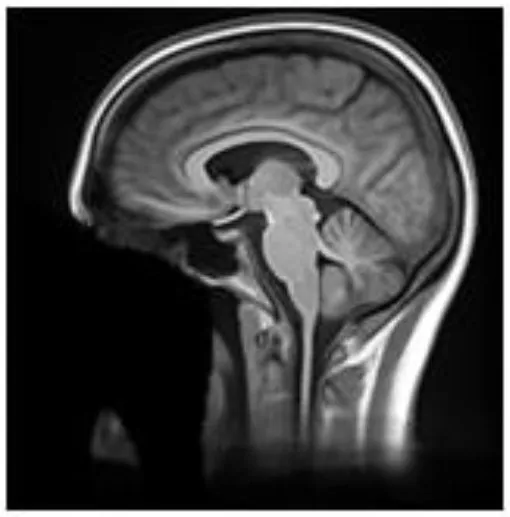

These 68 scans underwent defacing using each of the six defacing algorithms outlined in section Measuring Defacer Success. Following the defacing procedure, each image underwent an additional de-earring step using ear masks generated with fsl_deface (16). For each of the defacing sets, three of the twelve scans from each participant were randomly chosen for the recognition task, for a total test set of 108 defaced images. Two participants were used as “unknowns,” while photographs of the remaining four participants (including the three participants already personally familiar to the raters) were provided to human raters who then attempted to identify the 108 randomly presented defaced images. To help with recognition, each image contained three perspectives of the same 3D render (45° left, straight on, and 45° right of where the face would be; see Figure 1). For each image, raters were instructed to select one of six responses indicating whether they recognized the image as belonging to the person pictured in photograph 1, photograph 2, photograph 3, photograph 4, none of the four photographs, or whether there was not enough information available to make a confident recognition judgment (i.e., “Can't identify”).

FIGURE 1

www.frontiersin.org

Figure 1. True facial recognition task images. Top row: Sample original (pre-defaced) 3D rendered T1 image. Three perspectives of the head were generated, including 45° left, straight on, and 45° right. Bottom: The same image after undergoing defacing (in this case, pydeface) and de-earring. Consent was given by the participant to include their non-defaced MRI render in the publication.